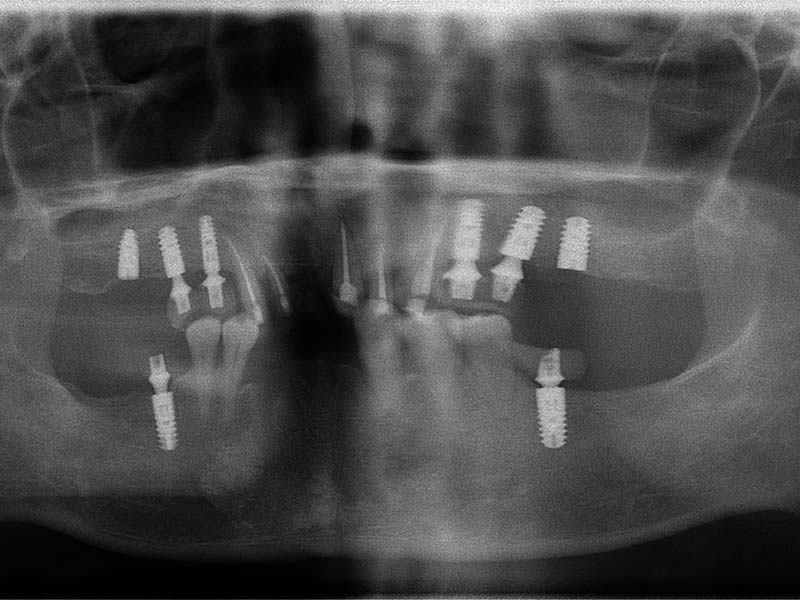

治療前

治療後